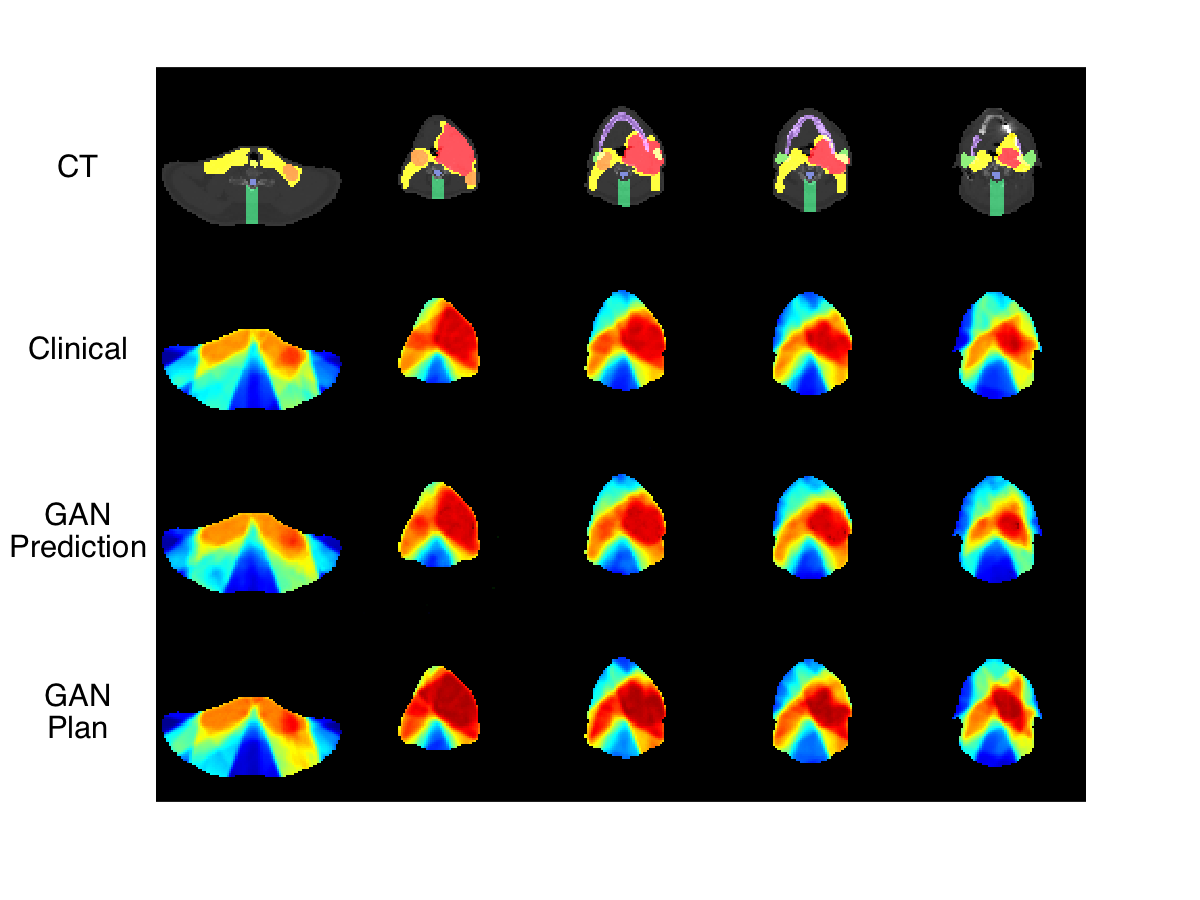

Knowledge-based planning (KBP) is an automated approach to radiation therapy treatment planning that involves first predicting a desirable treatment plan, before correcting it to a deliverable one. In this work, we propose a GAN approach to predicting desirable 3D dose distributions.